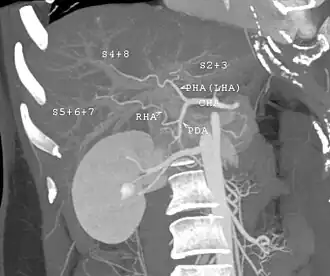

| Abdominal trauma resulting in a right kidney contusion (open arrow) and blood surrounding the kidney (closed arrow) as seen on CT | |

Kidneys

The kidneys may also be injured; they are somewhat but not completely protected by the ribs.[6] Kidney lacerations and contusions may also occur.[13] Kidney injury, a common finding in children with blunt abdominal trauma, may be associated with bloody urine.[13] Kidney lacerations may be associated with urinoma or leakage of urine into the abdomen.[4] A shattered kidney is one with multiple lacerations and an associated fragmentation of the kidney tissue.[4]